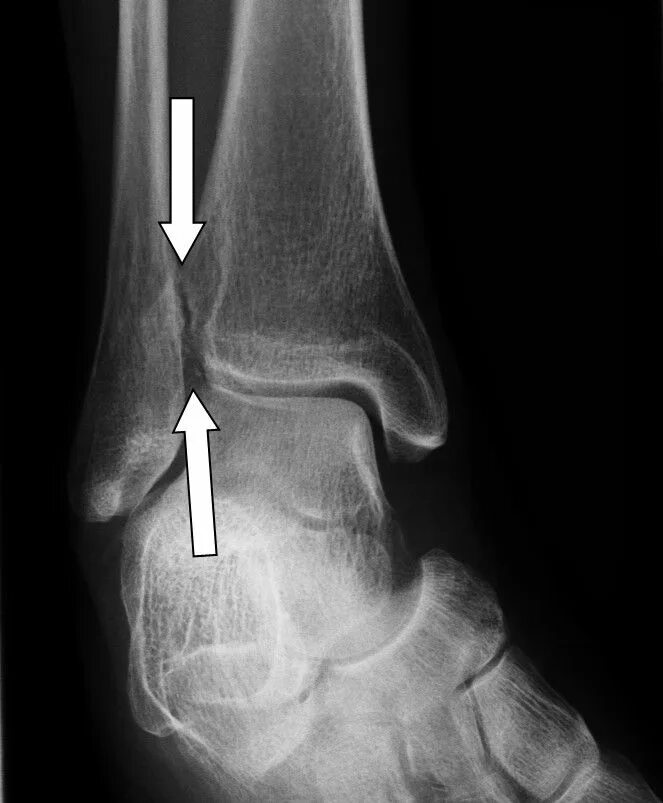

Артроз голеностопного сустава код